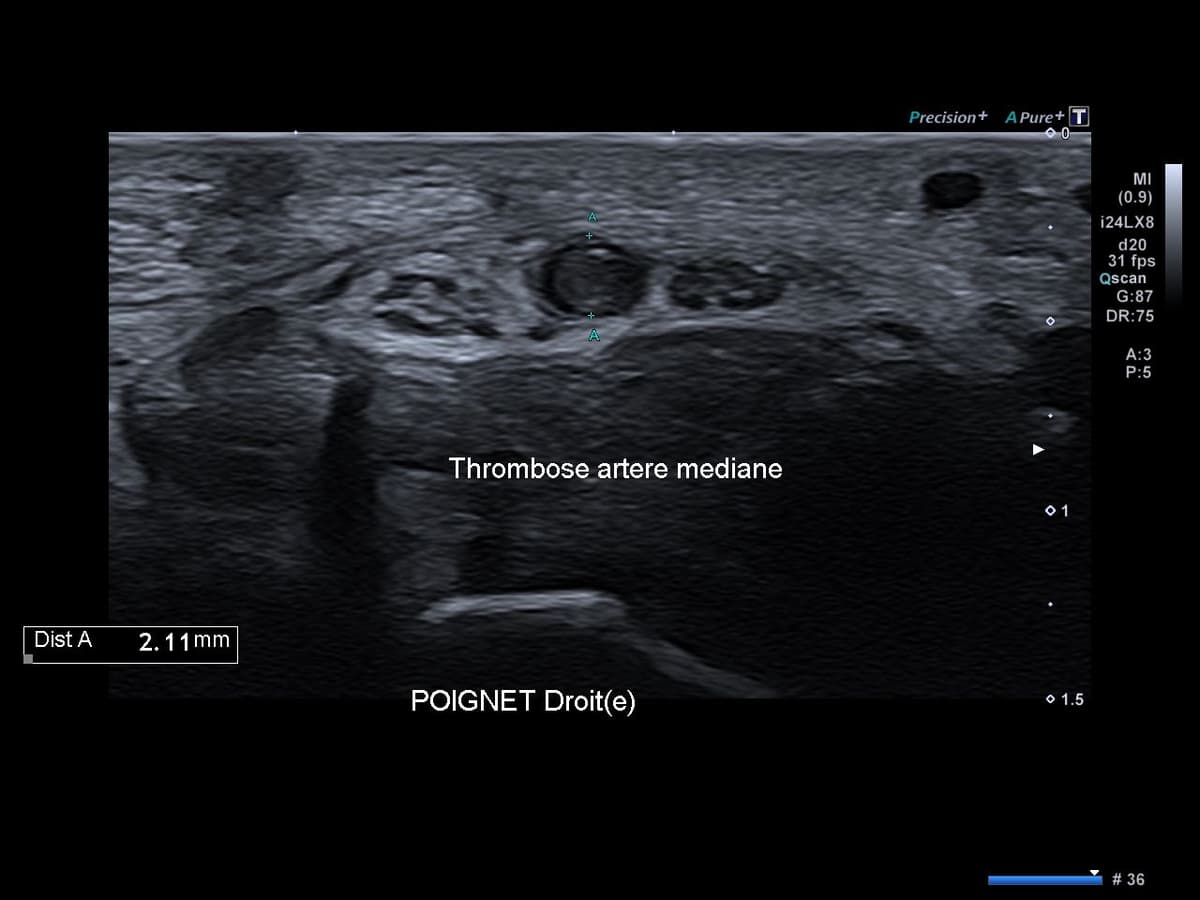

Thrombose de l'artère médiane du poignet

Douleur médiane spontanée du poignet révélant une pathologie vasculaire rare.

US